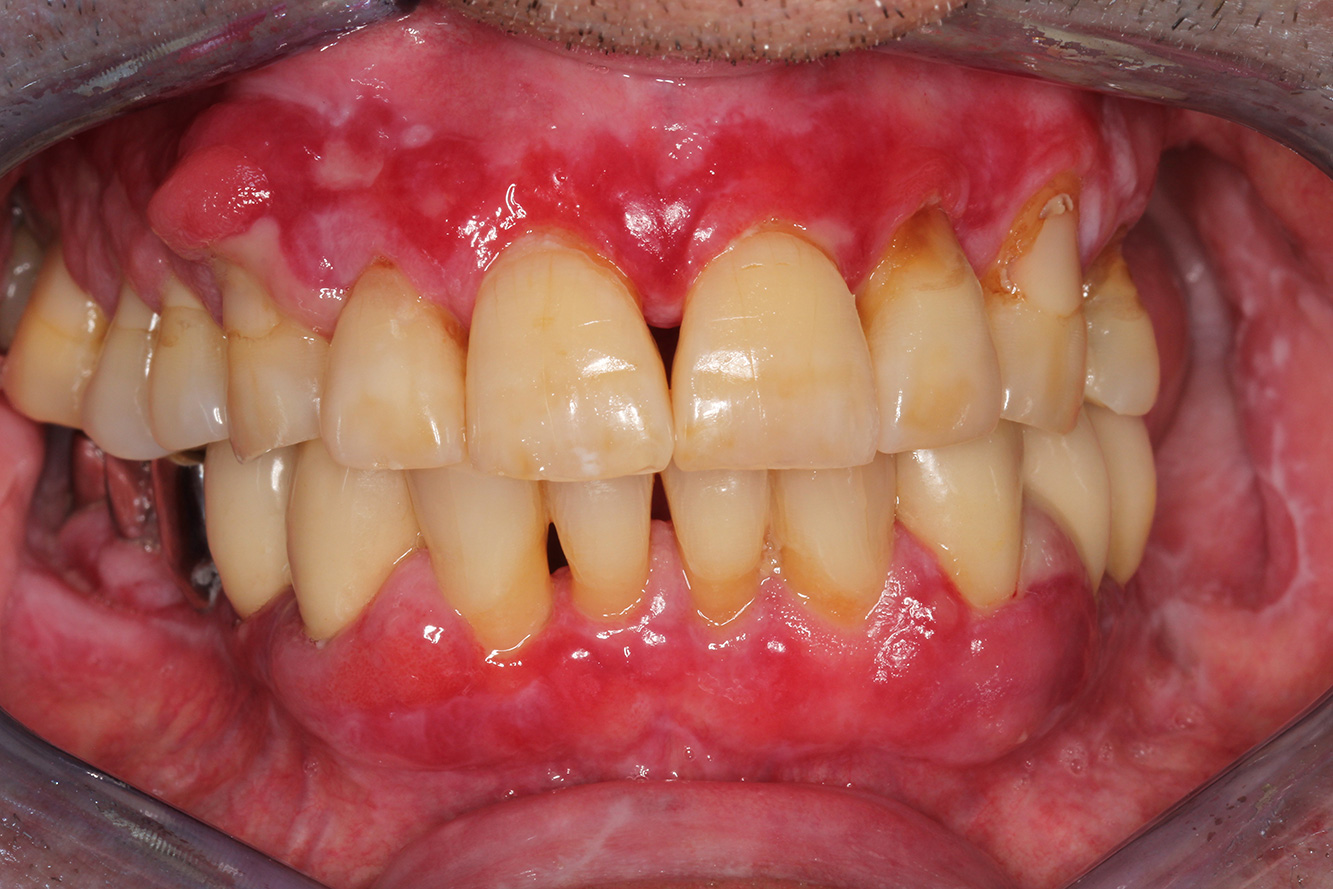

Ein 71-jähriger Patient mit Z.n. Nierentransplantation und Hypertonie (Bluthochdruck) stellt sich vor. Bedingt durch die Krankengeschichte ist eine Dauermedikation mit Cyclosporin, zur Unterdrückung der Immunabwehr, und Amlodipin, zur Blutdrucksenkung, erforderlich. Außerdem berichtet der Patient über empfindliches Zahnfleisch und Zahnfleischbluten. Aus mundgesundheitlicher Sicht zeigt sich ein saniertes Gebiss mit acht fehlenden Zähnen, ausgeprägte Gingivawucherungen, eine Parodontitis Stadium II, Grad B mit aktiven Taschen und eine initiale Wurzelkaries an Zahn 22. In der Kariesrisikoabschätzung wird ein mittleres Kariesrisiko (API 60) festgestellt. Für die Prophylaxesitzung lassen sich folgende Behandlungsempfehlungen ableiten. mehr Infos